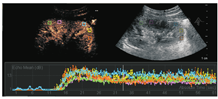

选取两组肾脏各5个感兴趣区域,每个ROI区域为正方形5 mm×5 mm选择框,选取注药后1 min图像,对其进行动态分析研究,应用QLAB软件,绘制肾皮质TIC曲线。对照组TIC曲线上升陡直,迅速达到峰值强度,而后缓慢下降至基础水平,见图2。实验组TIC曲线上升平缓,达到峰值强度延迟,下降缓慢,且峰值强度较低,造影剂消退较对照组快,见图3。

应用QLAB软件定量分析实验组及对照组TIC曲线,见图4,获得五组相关定量参数包括A、AUC、PI、TTP,分别取其均数。实验组及对照组的CEUS定量参数用两配对样本t检验比较,见表1。

CEUS目前已被广泛用于肾脏疾病,包括膀胱输尿管反流、糖尿病性肾脏疾病(diabetic kidney disease,DKD)、复杂性囊肿、肾脏肿瘤、慢性肾脏疾病(chronic kidney disease,CKD)、缺血性肾脏疾病和肾脏移植等肾脏病变随访,尚无研究评价CEUS对UPJO肾脏功能评估的有效性[14]。灌注参数中,TTP指超声造影剂开始进入感兴趣区肾皮质至达到强度峰值的时间,PI是指造影剂在一定时间内达到的最强信号强度,A指TIC曲线的上升支斜率,反映了肾皮质在血流灌注时血流速度和密度随时间的变化情况。AUC指一定时间内TIC曲线下面积,与微泡分布容积、血流速度及灌注时间有关,本研究截取注入造影剂后1min内的血流灌注情况,绘制TIC曲线。实验组TIC曲线上升平缓,达到峰值强度延迟,下降缓慢,且峰值强度较低。肾功能发生损害时,功能性肾血管收缩和全身血管扩张,导致血管阻力增加,肾脏皮质的灌注减低,单位时间的微泡容积减少,TIC曲线上升平缓。对照组和实验组的肾皮质血流灌注CEUS图像表明TIC可以通过肾灌注改变评价肾脏功能。

在本研究中,选取CEUS的等面积感兴趣区时选取均质、与声束垂直、保持同一深度、位置的外层肾皮质内,通过多点选取的方式,降低不同肾皮质内血流灌注差异造成偏倚。与对照组相比,实验组感兴趣区TIC曲线的AUC、PI、A均低于对照组,其中上升斜率A显著低于对照组,P<0. 05。达峰时间TTP实验组显著高于对照组,P<0. 05。实验组肾皮质血流灌注TTP显著延长,表明肾血管阻力增加,肾皮质血流灌注速度明显减慢,造影剂进入肾小球的时间延长;PI下降表示随肾血管阻力增加,实验组的肾脏血流灌注量下降,AUC受血流速度、微泡分布容积等的影响,其与肾皮质的血流量呈线性相关;TTP、PI变化导致TIC曲线上升斜率A降低[15]。此结论与其他学者针对大鼠单侧UPJO、早期肾损伤及慢性肾功能不全患者的研究结论不完全相符[7,10,16]。本研究评估了CEUS定量参数的诊断效率,TTP是肾脏血流灌注改变的敏感指标,其临界值为23. 459 s,其灵敏性高达92. 86%,是肾血流灌注减低、肾功能受损的敏感指标。由本研究可知TTP灵敏度高、特异度较低、阴性预测值为100%,漏诊率低,可以较为早期、及时的诊断敏感的诊断UPJO患儿肾功能不全。翻转ROC曲线获得上升斜率A的ROC曲线下面积0. 85,对于诊断肾脏功能未受损有统计学意义,灵敏度稍低,特异性较高,cut-off值为0. 92 dB/s,是诊断肾脏灌注正常、肾脏功能未受损的特异性指标。